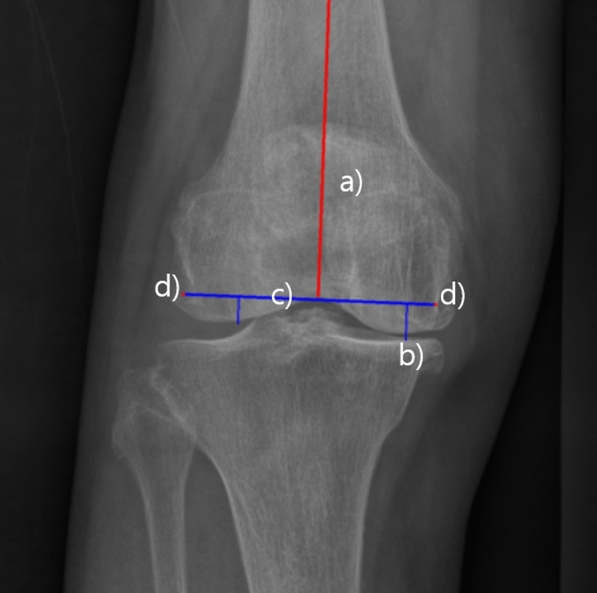

Methods: A total of 13,281 (2938 anteroposterior, 10,343 lateral) knee radiographs obtained from the authors' institute were utilized for model training, with 2302 (1034 anteroposterior, 1268 lateral) images set apart for validation and testing. The templating AI model integrates a pipeline composed of multiple steps for automated implant size estimation. To predict implant size, anterioposterior (AP) and lateral radiograph predictions were merged, selecting the smaller of the predicted sizes to prevent implant overhang. The model's size predictions were validated with 81 real TKA data set apart from the training data, and its accuracy was compared to that of manual templating by an orthopedic specialist. Predictions matching the actual implanted sizes were labeled "exact" and those within one size, "accurate." The influence of patient characteristics on the model's prediction accuracy was also analyzed. The measurement time elapsed for implant sizing was recorded for both the AI model and the orthopedic specialist. Implant position predicted by the model was validated by comparing insert locations with postoperative images.